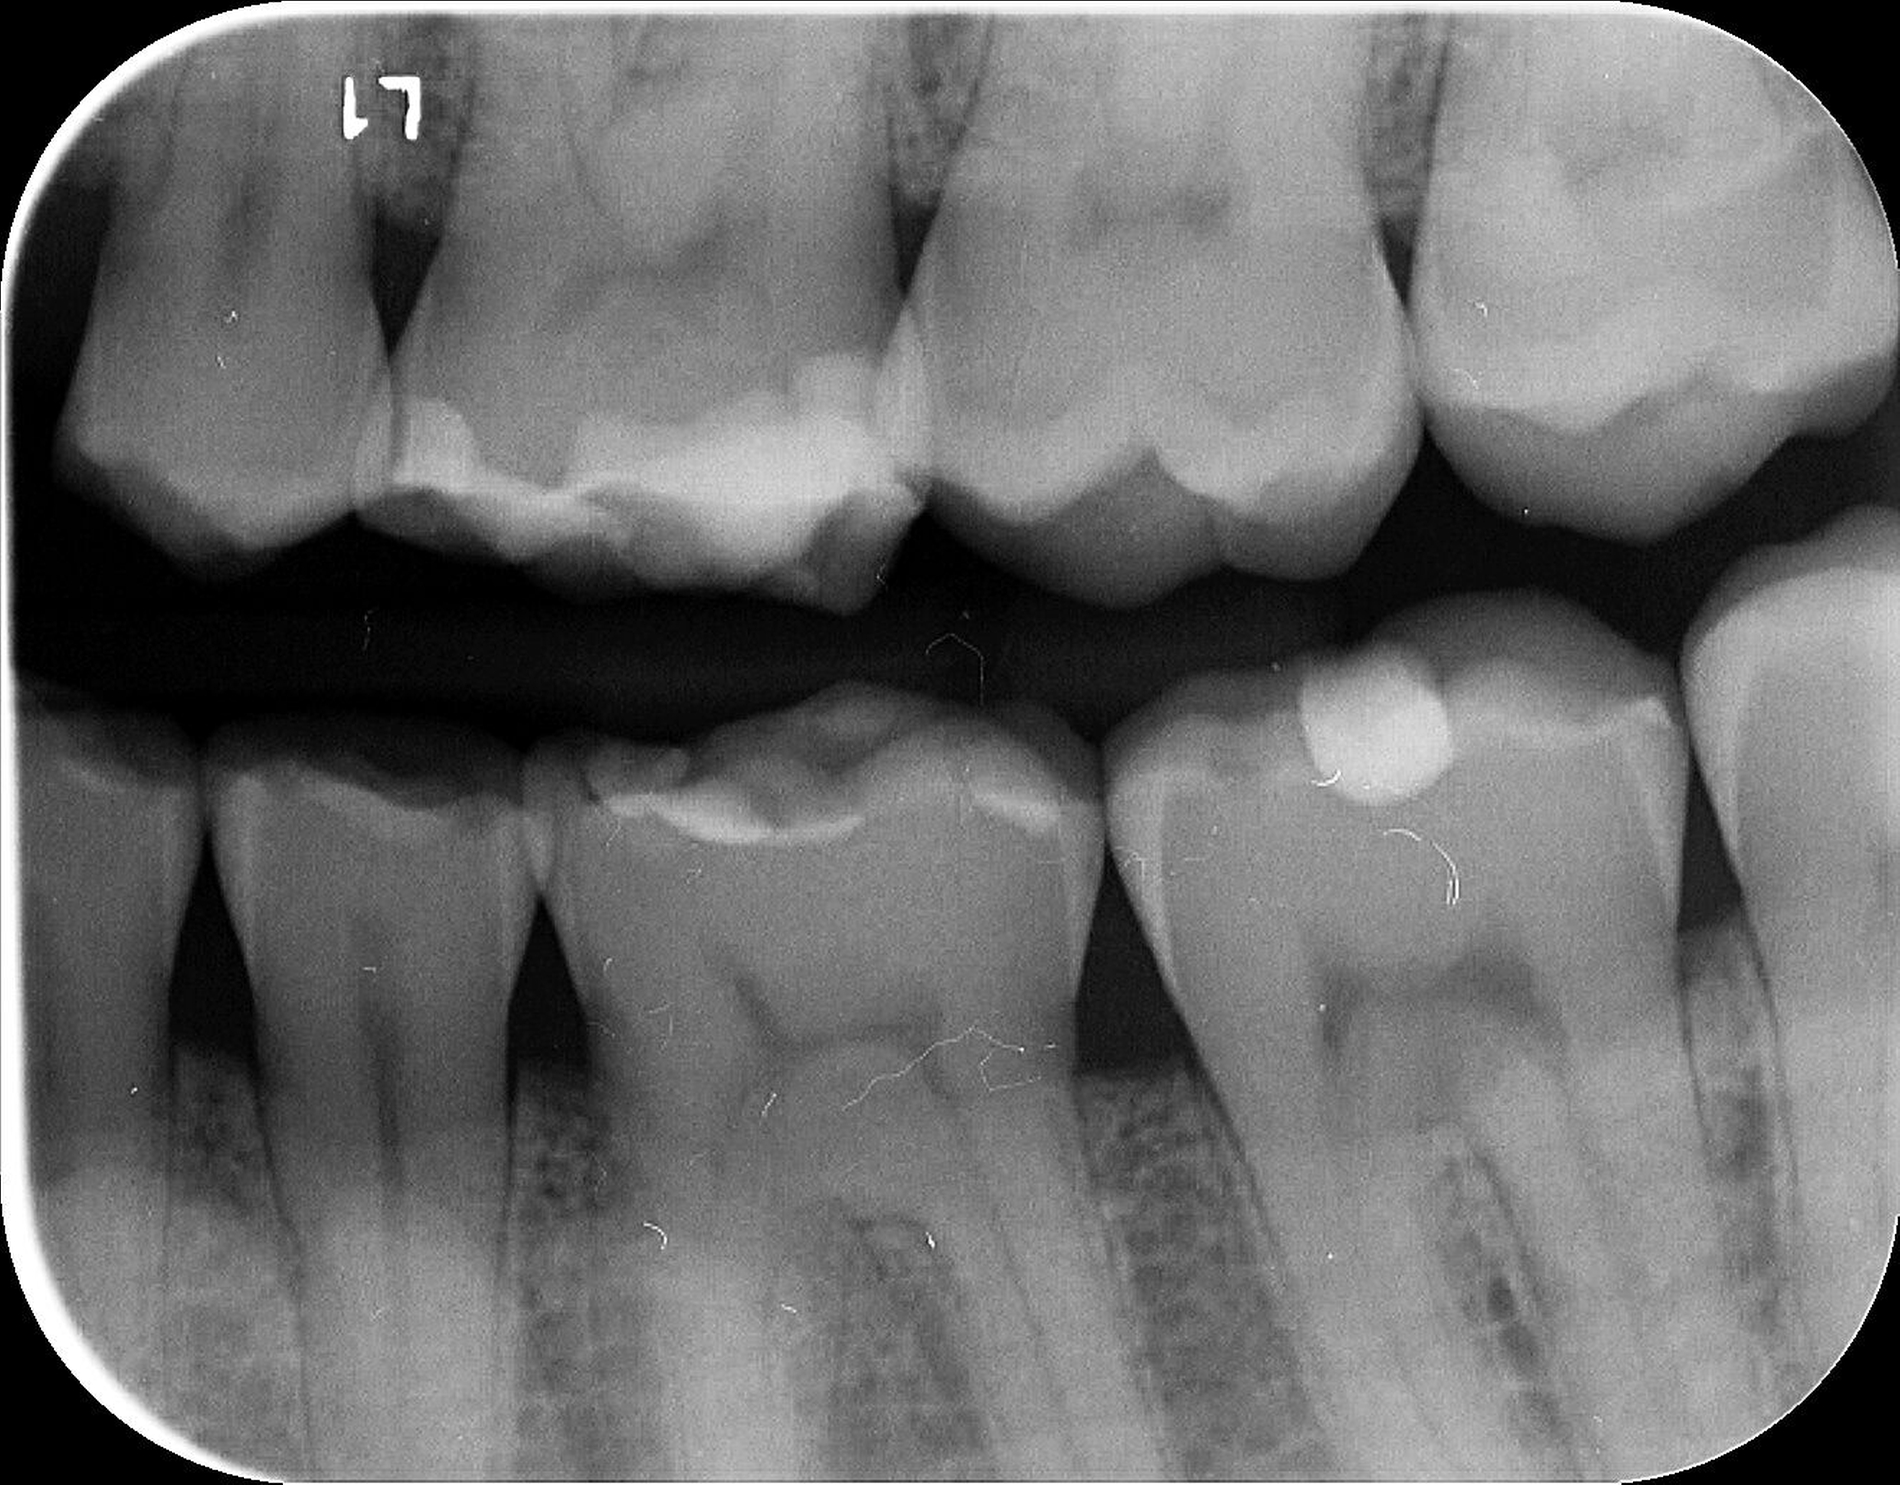

Das unter Beteiligung des Autors entwickelte Tooth Wear Evaluation System (TWES) 2.0 [Wetselaar et al., 2020] identifiziert per Screening Patienten mit erhöhten Verschleißwerten, vergleichbar mit dem PSI in der Parodontologie oder dem CMD-Kurzbefund. Bei auffälligen Werten folgt ein differenzierter Zahnverschleiß-Status einschließlich der Erfassung oraler und vestibulärer Substanzverluste [Wetselaar et al., 2016 sowie von Pathologie-Symptomen und einer strukturierten Diagnose [Tonetti und Sanz, 2019; Wetselaar, 2020]. Den Einsatz in der Praxis illustriert der in den Abbildungen beschriebene Patientenfall aus dem CMD-Centrum Hamburg-Eppendorf.

Im Beispiel ist daher die Diagnose ein generalisierter erheblicher und lokalisierter moderater pathologischer Zahnverschleiß überwiegend mechanischer und zudem chemischer Ursache. Die sich daraus ableitende Erkenntnis ist, dass in allen Sextanten Zähne freiliegende Dentinkerne aufweisen (generalisierter moderater Zahnverschleiß), dass darüber hinaus Zähne erheblich geschädigt und somit gefährdet sind, dass Merkmale eines pathologischen Geschehens bestehen – und dass als Ursache neben dem dominierenden Bruxismus ein Säureeinfluss hinzukommt.

Auch wenn Restaurationen nach Möglichkeit vermieden werden sollten, ist deren Verfügbarkeit für die Betroffenen individuell höchst wichtig, weil sie bestehende Schmerzen beseitigt, die verlorengegangene Kauleistung wiederherstellt und ästhetische und nicht zuletzt auch phonetische Einschränkungen aufhebt. Bei dem in den Abbildungen beschriebenen Fall korrelierte der erhebliche Zahnverschleiß mit der Lokalisation der Zahnschmerzen des Patienten. Direkte Restaurationen mit Kompositen hatten keinen Bestand. Die durchgeführte restaurative Behandlung hingegen hat Bestand, die Schmerzen waren danach umgehend verschwunden und sind seit zehn Jahren nicht wiedergekehrt.